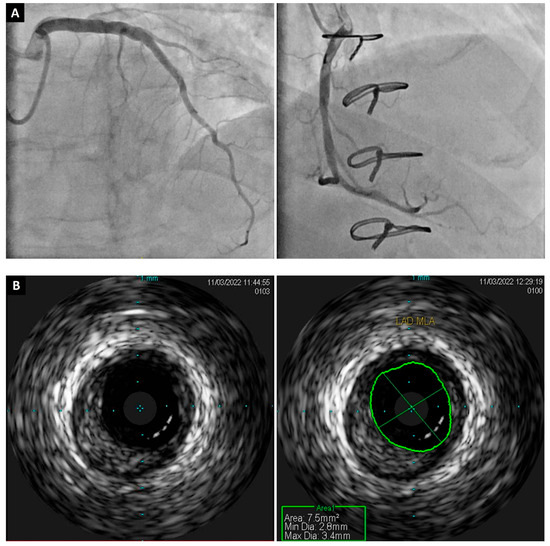

Though less widely available than SPECT, positron emission tomography (PET) is considered the gold-standard modality MPI, with the greatest accuracy, Figure 4 [91]. PET also utilizes the injection of radio-isotope-labeled drugs; however, these act by emitting positrons in target tissue [92]. PET allows for both the qualitative and quantitative assessment of myocardial perfusion [72]. Typically, contemporaneous CT imaging provides anatomical mapping [93]. Different radio-isotopes are used compared to SPECT, usually rubidium-82 or ammonia-13, to assess perfusion and, due to their short half-lives, usually require an onsite generator or cyclotron [93].

Figure 4.

Moderate to large reversible perfusion defect (white arrows) in the anterior and inferolateral wall showed using positron emission tomography (A) and computed tomography cardiac perfusion test (B). Coronary allograft vasculopathy was confirmed with invasive coronary angiography; this study showed a severe obstruction (white circle) in the mid circumflex artery (C).